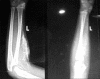

X-ray of left forearm with elbow joint (anteroposterior and lateral views) showing ossification in the dermis and subcutaneous tissue in February 2010

X-rays of forearm with elbow joint (anteroposterior and lateral views) showing ossification in the dermis, subcutaneous tissue, and muscles